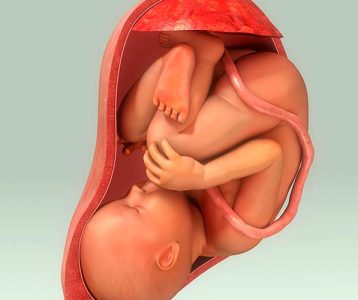

De acordo com o Ministério da Saúde, 1 a cada 10 nascimentos no Brasil ocorre antes da hora, colocando o país entre os 10 com maior índice de partos prematuros no mundo. A prematuridade é uma condição que pode trazer diversas complicações para o recém-nascido, já que os órgãos ainda não estão totalmente desenvolvidos. A chegada de um bebê antes do tempo considerado normal, bem como a expectativa do que pode acontecer durante o nascimento, o tempo de UTI e o desenvolvimento do bebê são pontos importantes do parto prematuro.

Segundo o médico pediatra e neonatologista Juhir Paulo Braglia Junior, professor da UniSul/Inspirali, o bebê é considerado prematuro quando nasce abaixo de 37 semanas de idade gestacional. Além disso, existem diferentes graus de prematuridade. Prematuro extremo são bebês que nascem antes de 28 semanas; e prematuro muito pré-termo são os que nascem entre 28 e 32 semanas. “Já o prematuro moderado chega entre 28 e 37 semanas, sendo que entre 34 e 37 são bebês pré-termo tardio”, explica.

A prematuridade pode representar risco para o bebê dependendo do grau e das causas, das condições de gestação e do parto. Para a mãe, representa risco quando for causada por determinadas enfermidades como doença hipertensiva específica da gestação (DHEG) e descolamento prematuro da placenta (DPP).